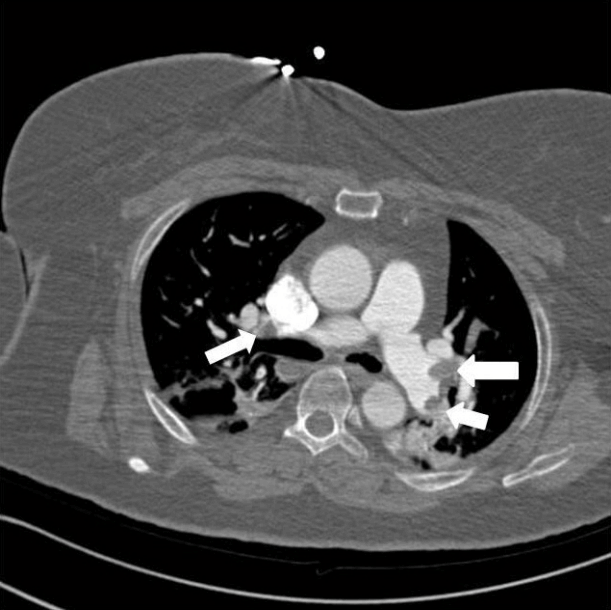

Emergency transesophageal echocardiography (TEE) was performed. The test revealed a hypokinetic dilated right ventricle (RV) and a D-shaped left ventricle (LV) (Figure 2). LV systolic dysfunction was noted without inferior vena cava (IVC) collapsibility. Tricuspid regurgitation was found with 49 mmHg pressure gradient (Figure 3). Considering the decreased EtCO2, elevated PaCO2, and TEE findings, PTE was suspected. Cardiopulmonary resuscitation until return of spontaneous circulation was repeated 3 times. HR was maintained at 120 beats/min, SBP at 150 mmHg, and SpO2 at 70%. Following consultation with cardiology and neurosurgery, we decided to use thrombolytics after diagnosis by multidetector computed tomography (MDCT). MDCT revealed occlusion of both pulmonary arteries with multiple pulmonary thromboembolisms and atelectasis in both lungs, consistent with a diagnosis of acute PTE (Figure 4). DVT was not observed elsewhere. The D-dimer level from a sample obtained in the operating room was above 3,200 ng/ml and troponin I was 0.02 ng/ml.